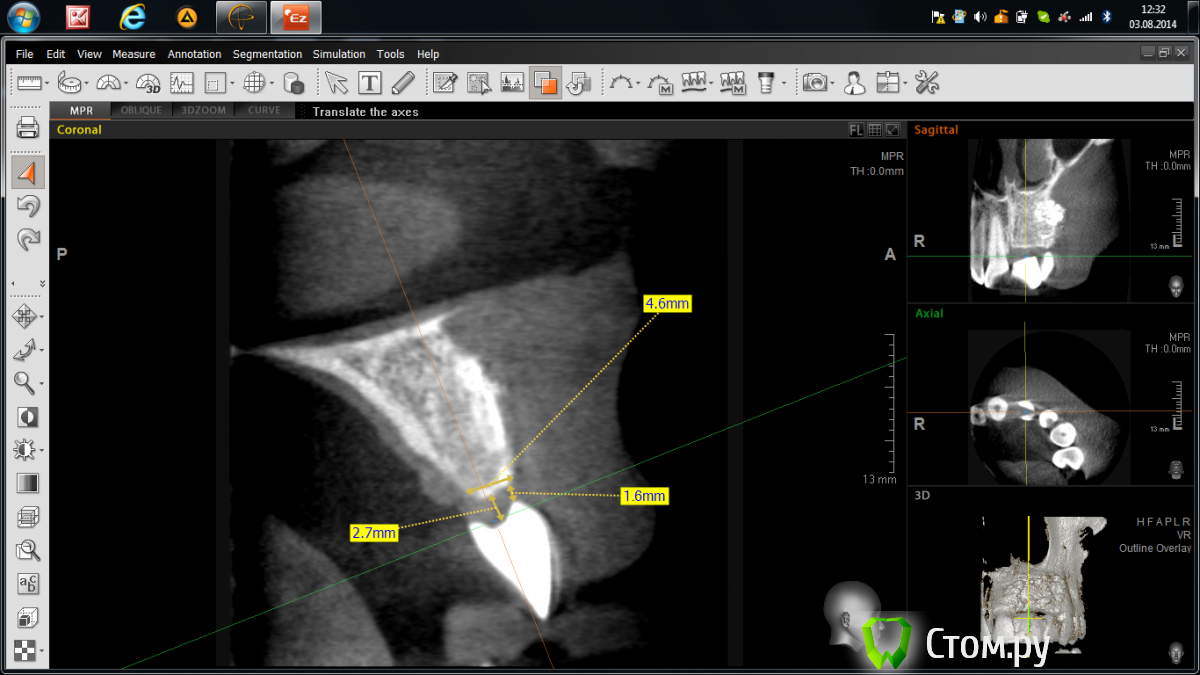

Abuk Опубликовано 3 августа, 2014 Поделиться Опубликовано 3 августа, 2014 Добрый день,коллеги.Горит,помогайте! Года 2 назад,когда я был молод,красив и малоопытен)),консультировал пациентку,на предмет восстановления имплантатами двух отсутствующих зубов:2.1,2.2; на месте которых висел композитный пртез. Отрофия кости была заметна невооруженным глазом,КТ подтвердило. Начинали с 3D пластики.Старые фото, пока, не нахожу((( Ширина кости была около 3 мм по 11-13 мм гребню.После операции ,спустя 4 месяца,пациентка ушла в декрет и пропала на 2 года.Ныне сделав рентген - шаблон,отправил на КТ(.Ошибки я учел,по поводу костной пластики).Недостаток в верхушке гребня и воостановление десневого сосочка-задачи,которые предстоит решить.Посоветуйте:возможно ли1.без повторной агрессивной костной пластики2.или можно ограничиться только работой с мягкими тканями???????? Ссылка на комментарий